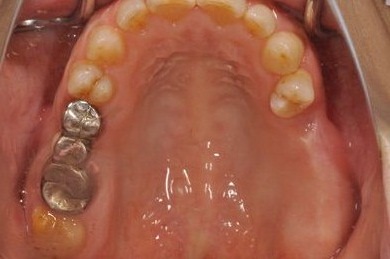

| 性別/年齢 | 女性 / 59歳 | ||||||||||||||||||||||||||||||||

| 主訴 | 奥歯がないので、インプラントか入れ歯の相談をしたい。 | ||||||||||||||||||||||||||||||||

| 治療方針 | 左上奥ソケットリフトにて上顎洞を拳上、骨再生法を行い、インプラント治療を可能にする。 | ||||||||||||||||||||||||||||||||

| 治療内容 | インプラント4本(GBR)、ハイブリッドセラミック4本 | ||||||||||||||||||||||||||||||||

| 総治療費 | 1,680,000円 | ||||||||||||||||||||||||||||||||

| 治療期間 | 11ヶ月 |